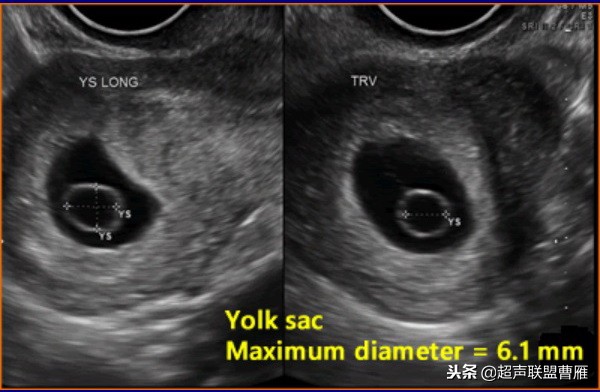

卵黄囊的大小与形态异常与胚胎的发育是否正常关系密切。卵黄囊增大,直径超过6.1cm,胚胎的预后不良。

有的文献将卵黄囊内径的最大限度定为6.1mm

孕龄7+5周卵黄囊10.3mmx9.5mm,胚胎死亡

卵黄囊的大小与形态异常与胚胎的发育是否正常关系密切。,形态异常的卵黄囊预后不良。